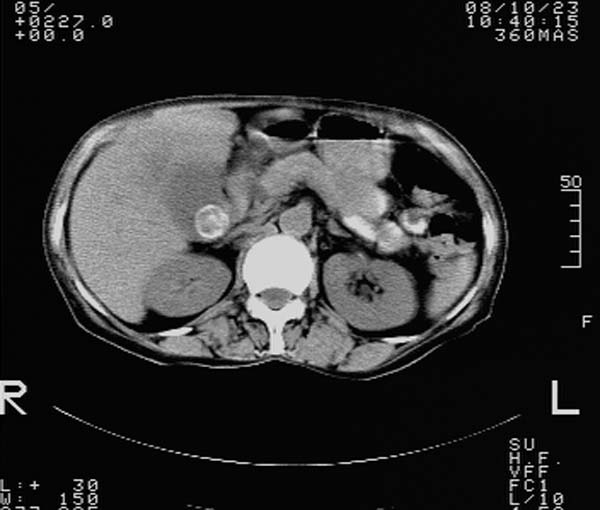

f,67y。反复右上腹痛。余无异常。

前五幅未服造影剂。后面图像有上传重复的。请战友们发表意见。

胆囊结石、胆囊癌伴邻近脏器受侵,不除外黄色肉芽肿性胆囊炎,建议增强扫描。肝多发囊性占位性病变,囊肿或囊性转移。

胆囊内结石,胆囊壁不规则增厚,胆囊胃窦区解剖结构欠清晰,楼主提示为少见病,考虑bouveret综合征?黄色肉芽肿性胆囊炎?肝内多发低密度占位,建议增强或b超